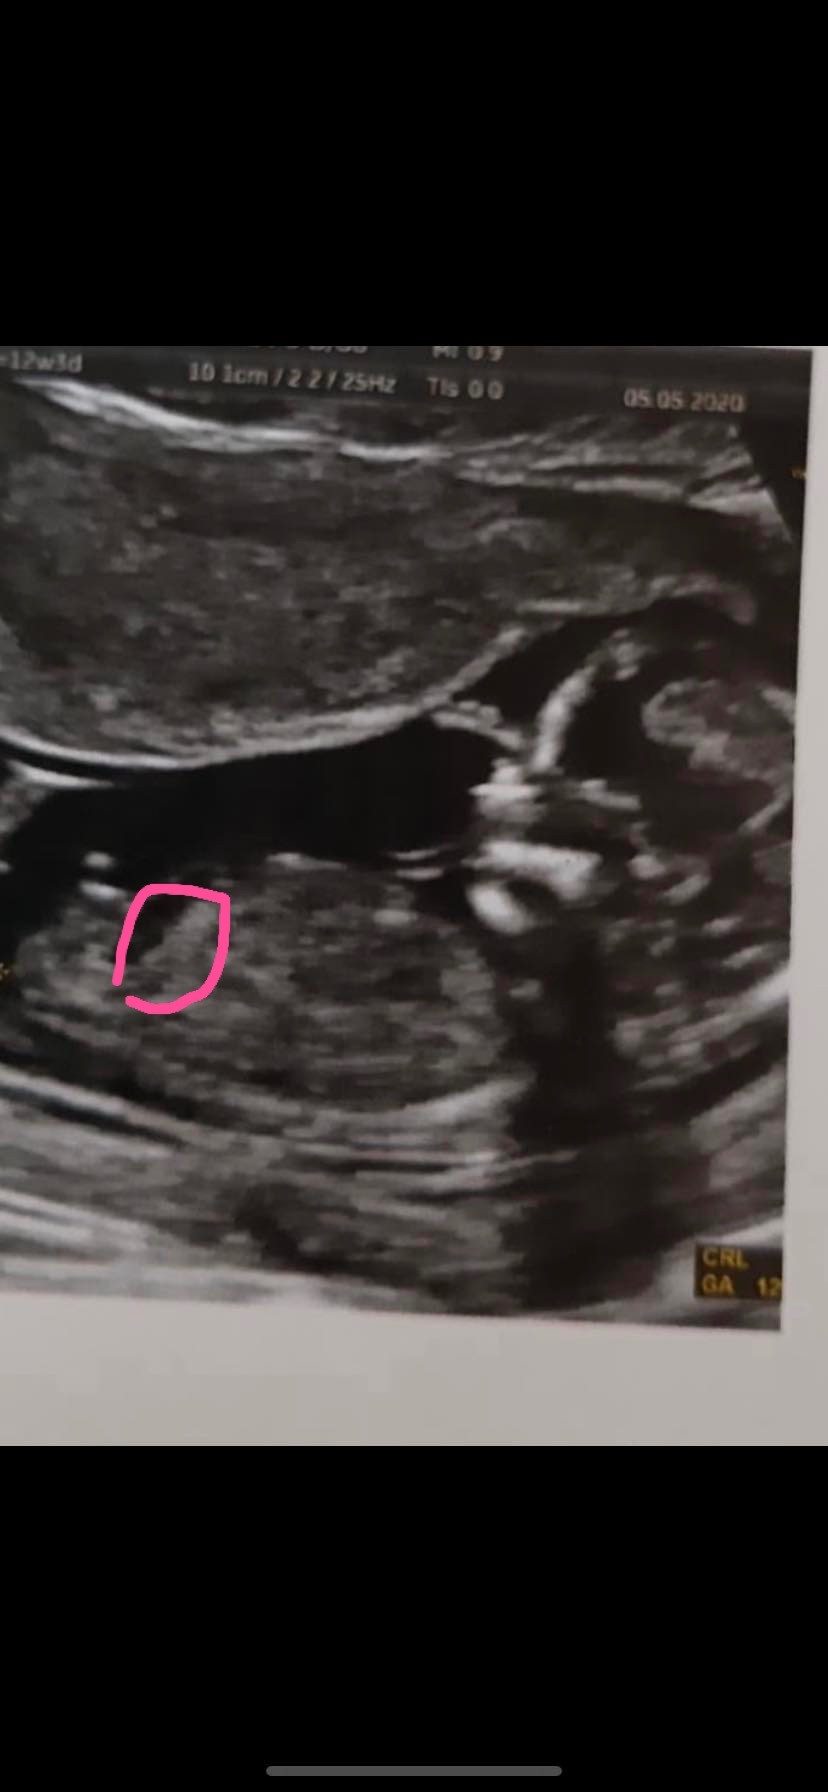

Na pierwszym zdjęciu bym powiedziała że dziewczynka ale już na drugim chłopak[emoji6]U mojego tak to wygląda....

Podobno ma.byc chłopak...

Na drugim ma chyba bardziej pupke podwinięta. Niech będzie co chce, byle zdrowe przy tych moich anomaliachNa pierwszym zdjęciu bym powiedziała że dziewczynka ale już na drugim chłopak[emoji6]

Ja bym obstawiała chlopakazazdroszczę wam dziewczyny takich zdjęć,u mnie nie widać wyrostka jedynie ta kulka.. nie daje mi ona spokoju.. Jak myślicie jest to stopa czy może jakimś cudem to być ta kulka na wyrostku płciowym?Czy to może dla was baba?U ciebie bubuś widać bardzo wyraźnie wyrostek i kulkę skierowana do gory i tez bym obstawiała chłopakaNa co powinnam bardziej patrzec?Zobacz załącznik 1130951Zobacz załącznik 1130950